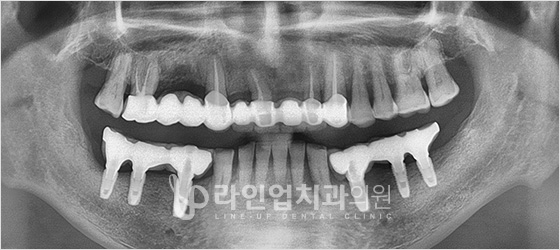

치료전 Before

치료후 After

下臼齿种植牙